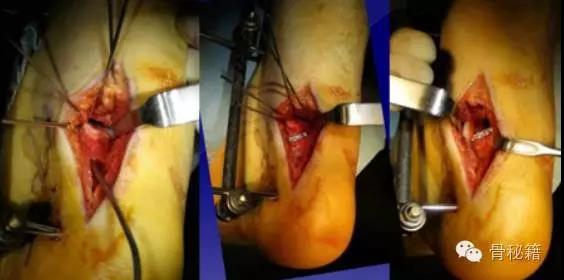

手术入路1、内侧入路比较安全,注意大隐静脉和隐神经

骨折十分粉碎时可采用内踝截骨事先可进行螺钉的拧入,类似鹰嘴截骨

2、外侧入路